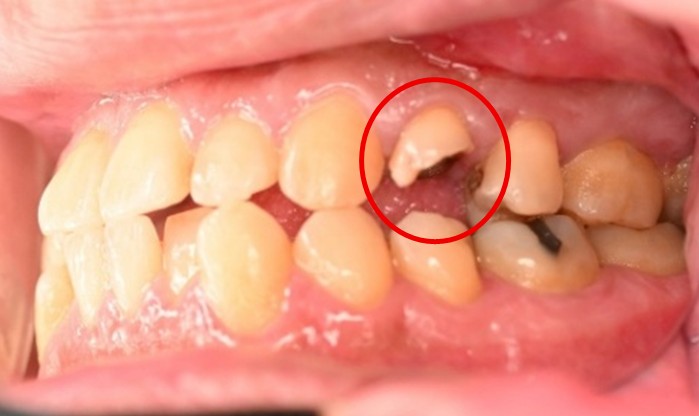

女性 Aさん 50代 (オールセラミック冠)

主訴

色が変わった上前歯をきれいにしたい。

治療内容

根管治療をし、オールセラミック冠を被せました。

所感

神経が取り除かれ、大きく詰め物がされていました。詰め物及び歯自体が変色し、虫歯になっていました。根管治療をし、ファイバーコアを入れ、オールセラミック冠を被せました。自分の歯は、捻転していましたが、被せ物により歯並びを改善することができました。

オールセラミック冠1本:¥104,500(税込)

Before

After